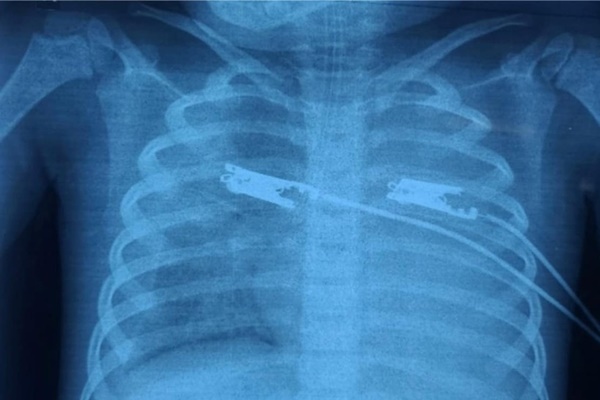

Bệnh nhân vào viện với biểu hiện sốt dài ngày, tổn thương đa cơ quan: Suy hô hấp, suy tuần hoàn, tổn thương gan thận, ức chế tủy xương. Cả 2 trường hợp đã được điều trị tích cực từ tuyến dưới nhưng chưa tìm ra được căn nguyên vi sinh gây bệnh vì vậy điều trị không đáp ứng.

Các bệnh nhân chuyển lên điều trị tại khoa Hồi sức truyền nhiễm trong tình trạng suy đa tạng (suy hô hấp, suy tuần hoàn, suy gan). Các bác sỹ đã khám và phát hiện vết loét do sốt mò điển hình, được điều trị kháng sinh đặc hiệu(Doxycyclin) và điều trị hỗ trợ suy tạng.

Ảnh minh họa